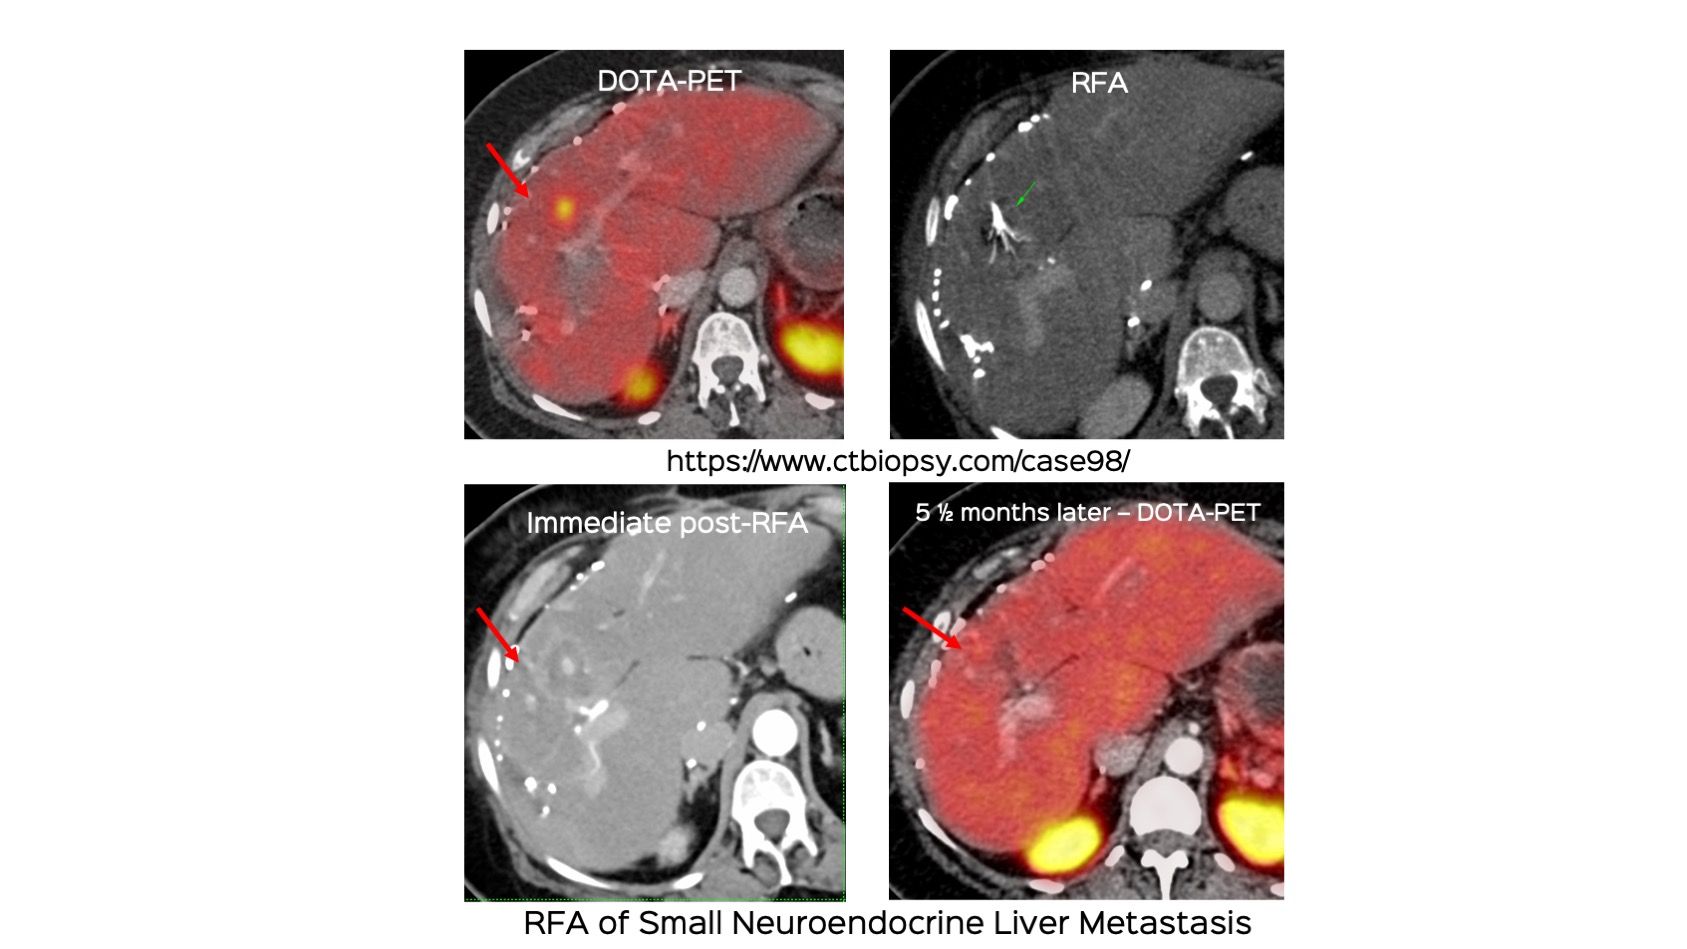

Case 98: Small Liver Lesion Radiofrequency Ablation (RFA)

Bhavin Jankharia - 25 July 2022